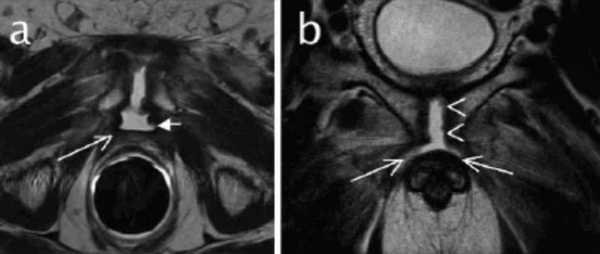

Подострый остеомиелит на МР-скане и обычной рентгенограмме: отслойка надкостницы (наконечник), гнойный очаг (стрелки)

МРТ-признаки остеомиелита лонных костей: расширение сочленения и скопление жидкости с формированием параартикулярных затеков (длинные стрелки), разрастание грануляционной ткани (короткие стрелки), Т2-ВИ, аксиальная (а) и коронарная (в) плоскости